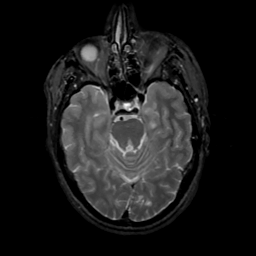

MR Study #16, June 23, 1991 -- Slice #17